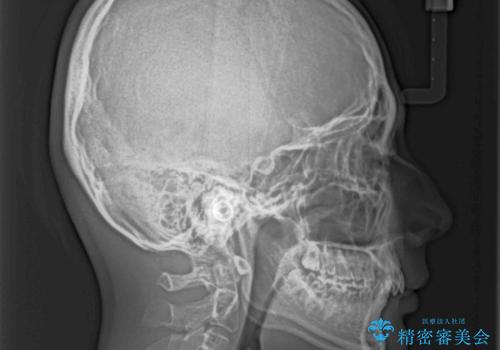

下顎前歯が全て隠れてしまうほどの深い咬合で、左右の奥歯は1歯対1歯で咬み合う状態でした。

前方に移動している上顎臼歯を補助装置にて遠心移動させることで1歯対2歯の臼歯咬合を目指し、同時に深い咬合を改善していくこととしました。